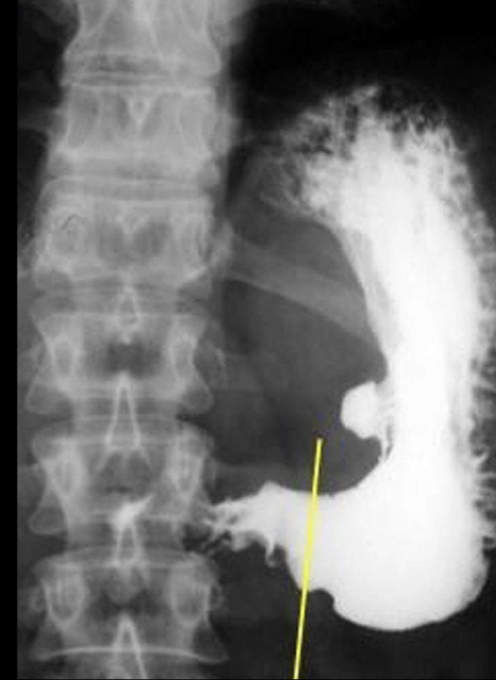

A

Ulcera